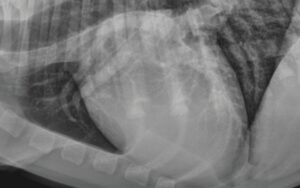

Ho do tim to

- Khi tim giãn hoặc phì đại, có thể chèn vào đường thở gây ho.

→ Dùng Furosemid giúp đẩy bớt nước ra ngoài, giảm thể tích máu và áp lực tim, làm tim co lại, giảm chèn ép khí quản và giảm ho.